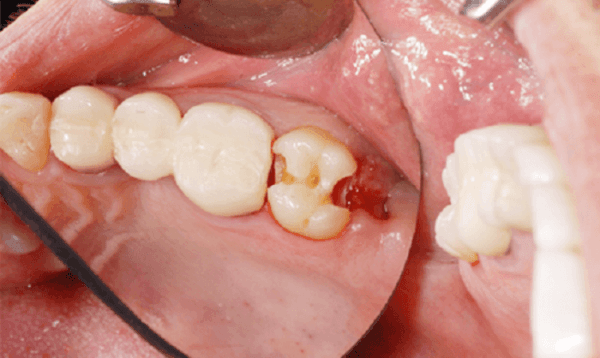

Sâu răng lồi thịt là một bệnh lý thường gặp ở những người sâu răng lâu ngày. Nguyên nhân là do bệnh sâu răng để lâu không điều trị hoặc không được điều trị triệt để nên sinh ra nhiễm trùng, biến chứng răng sâu lồi thịt.

Dấu hiệu nhận biết sâu răng lồi thịt là tại khu vực răng sâu, nướu sẽ xuất hiện một cục thịt lồi lên do niêm mạc bị sưng to. Cục thịt này không chỉ gây cảm giác khó chịu mà còn gây nhiều hệ lụy tới sức khỏe cho người bệnh: